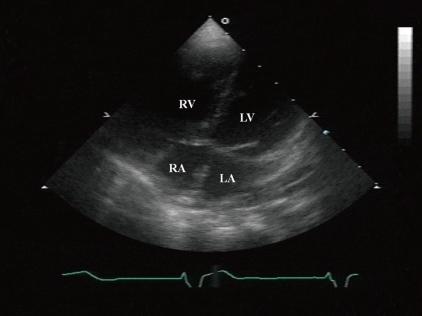

Partial anomalous pulmonary vein connection (PAPVC) is a rare congenital abnormal cardiac defect involving the pulmonary veins draining into the right atrium (RA) directly or indirectly by venous connection. Ninety percent of PAPVCs are accompanied by atrial septal defect (ASD). To our knowledge, there is no previous report of PAPVC with ventricular septal defect (VSD) without ASD in Korea, and in this paper, we report the first such case. A 2-day-old girl was admitted into the Chonnam National University Hospital for evaluation of a cardiac murmur. An echocardiogram revealed perimembranous VSD without ASD. She underwent patch closure of the VSD at 5 months of age. Although the VSD was completely closed, she had persistent cardiomegaly with right ventricular volume overload, as revealed by echocardiography. Three years later, cardiac catheterization and chest computed tomography revealed a PAPVC, with the right upper pulmonary vein draining into the right SVC. Therefore, correction of the PAPVC was surgically performed at 3 years of age. We conclude that it is important to suspect PAPVC in patients with right ventricular volume overload, but without ASD.

部分性肺静脉异位连接(PAPVC)是一种罕见的先天性心脏缺陷,涉及肺静脉通过静脉连接直接或间接引流至右心房(RA)。90%的PAPVC伴有房间隔缺损(ASD)。据我们所知,韩国此前尚无无ASD的PAPVC合并室间隔缺损(VSD)的报道,本文报告首例此类病例。一名2日龄女童因心脏杂音入院全南国立大学医院评估。超声心动图显示为膜周部VSD,无ASD。她在5个月大时接受了VSD修补术。尽管VSD完全闭合,但超声心动图显示她仍有持续的心脏扩大及右心室容量超负荷。3年后,心导管检查和胸部计算机断层扫描显示存在PAPVC,右上肺静脉引流至右头臂静脉。因此,在3岁时对PAPVC进行了手术矫正。我们得出结论,对于右心室容量超负荷但无ASD的患者,怀疑PAPVC很重要。